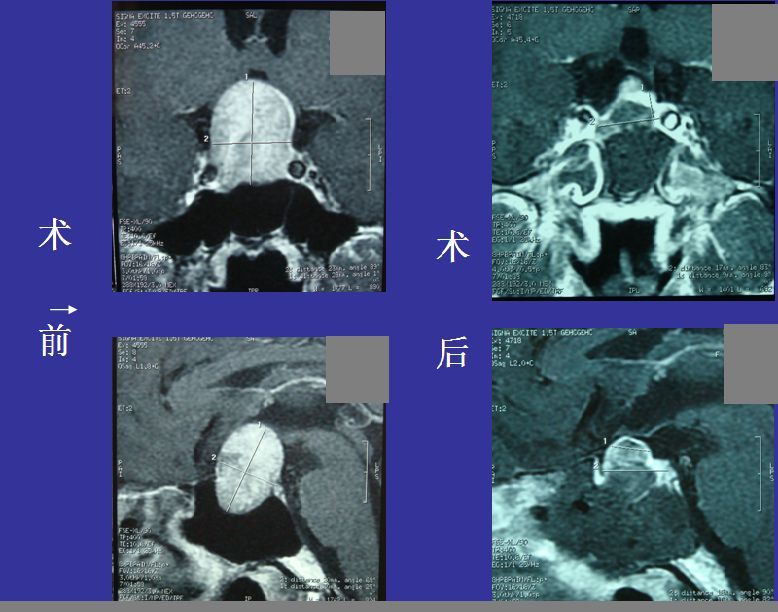

垂体巨大腺瘤

男性患者,术前视力左侧0.6右侧0.6,术后视力左侧1.0右侧0.8.术前和术后一周检查,显示肿瘤全切,原肿瘤信号变为填塞明胶海绵信号。

垂体腺瘤